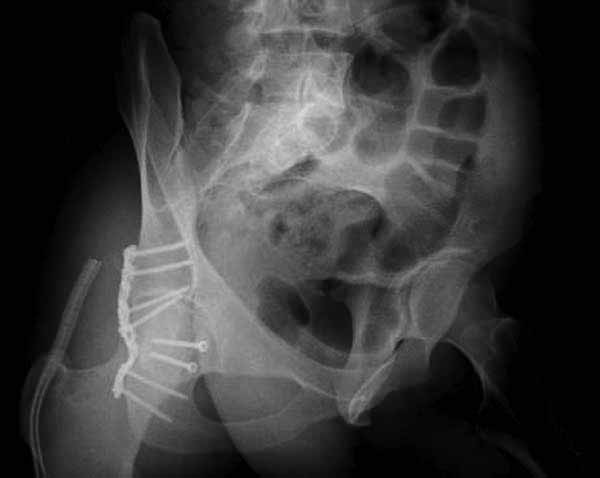

Движение в суставе, отведение - 35 гр., згибання- 90 гр., внутр. ротация- відсутня, зовн. ротація - 20 гр. Ещё снимки:

Перелом головки бедренной кости. Эндопротез?

Оставить как есть ненадо, т. к. отломок перевёрнут на 180 градусов, а чтобы делать остеосинтез время упущено, большая вероятность что закончится асептическим некрозом, в приложенном файле подходящий эндопротез для него.

Еще снимки